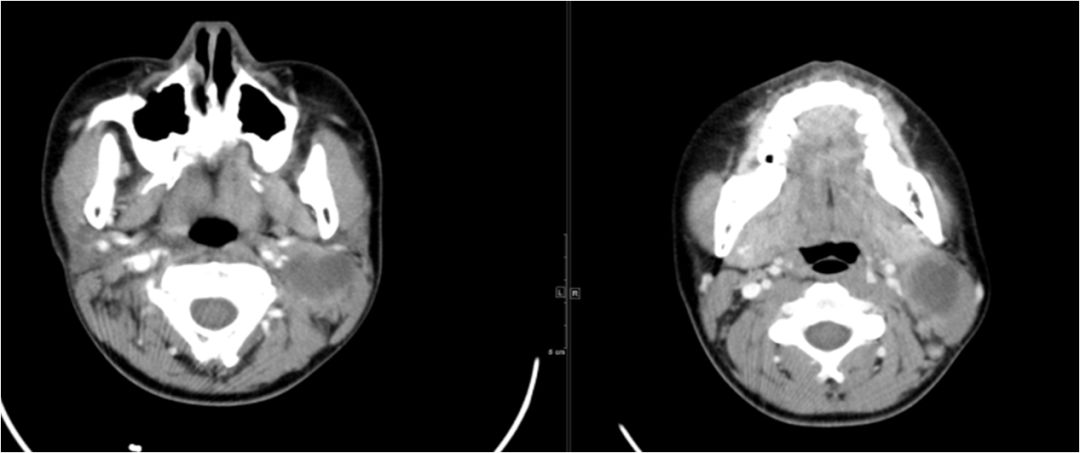

15 多间隙受累

(1)左下后牙疼痛11天余,颈部肿胀10天。

(2)右侧颌面部弥漫性肿胀1月余。